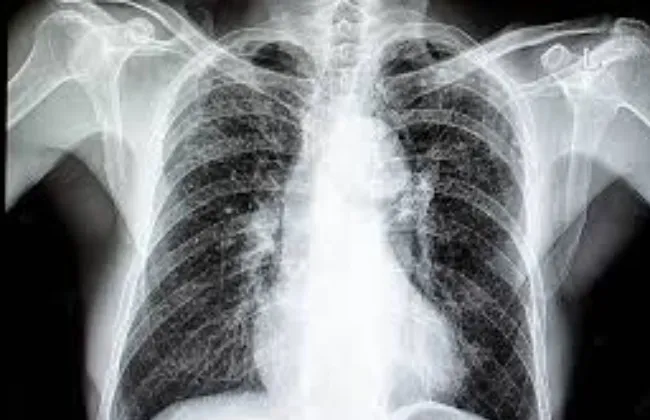

الصحة العالمية توافق على أول اختبار لتشخيص السل خلال ساعات و يلبى معايير المنظمة

قالت منظمة الصحة العالمية فى بيان لها ، إنها منحت الموافقة المسبقة على اختبار التشخيص الجزيئي

لمرض السل المسمى

Xpert® MTB/RIF Ultra

وهو أول اختبار لتشخيص مرض السل واختبار حساسية المضادات الحيوية يلبي معايير الموافقة

المسبقة لمنظمة الصحة العالمية

وأضافت، إن مرض السل هو أحد الأمراض المعدية القاتلة الرئيسية في العالم، حيث يتسبب في وفاة أكثر

من مليون شخص سنويا ويفرض أعباء اجتماعية واقتصادية هائلة، وخاصة ....